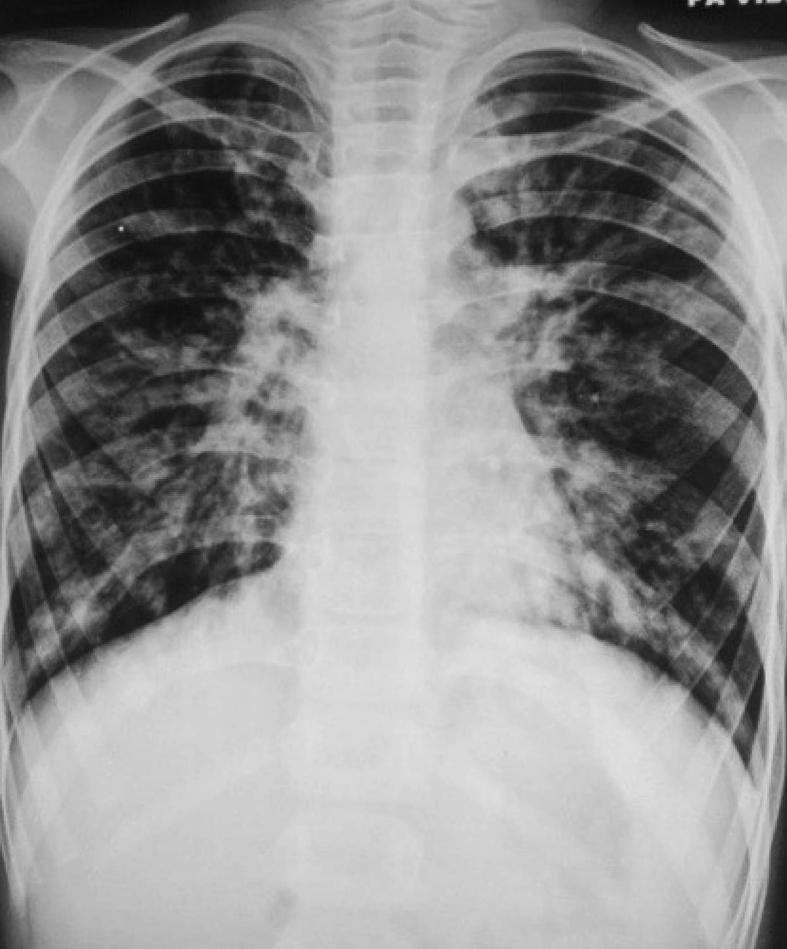

Allergic bronchopulmonary aspergillosis (ABPA) is a complex hypersensitivity reaction in patients with asthma or cystic fibrosis (CF), which is associated with bronchi colonized by the fungus Aspergillus species, most often Aspergillus fumigatus. ABPA is an important consideration for asthmatics that do not respond to asthma management or with recurrent chest infections and deteriorating lung function in children with cystic fibrosis. We present two cases of non CF bronchiectasis associated with ABPA who presented to our hospital with recurrent hospitalisations of undiagnosed aetiology.

变应性支气管肺曲霉病(ABPA)是哮喘或囊性纤维化(CF)患者发生的一种复杂的超敏反应,与曲霉菌属真菌(最常见的是烟曲霉)定植于支气管有关。ABPA是那些哮喘治疗无反应或反复出现肺部感染且肺功能恶化的囊性纤维化儿童哮喘患者需要重点考虑的疾病。我们报告两例与ABPA相关的非CF支气管扩张症患者,他们因病因不明反复住院而前来我院就诊。